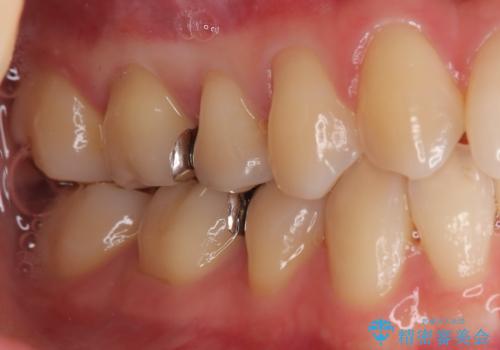

- 「銀歯を白しくしたい」を主訴に来院された患者さんです。

銀歯を外し、虫歯を除去した後にハイブリッドインレーで治療を行いました。